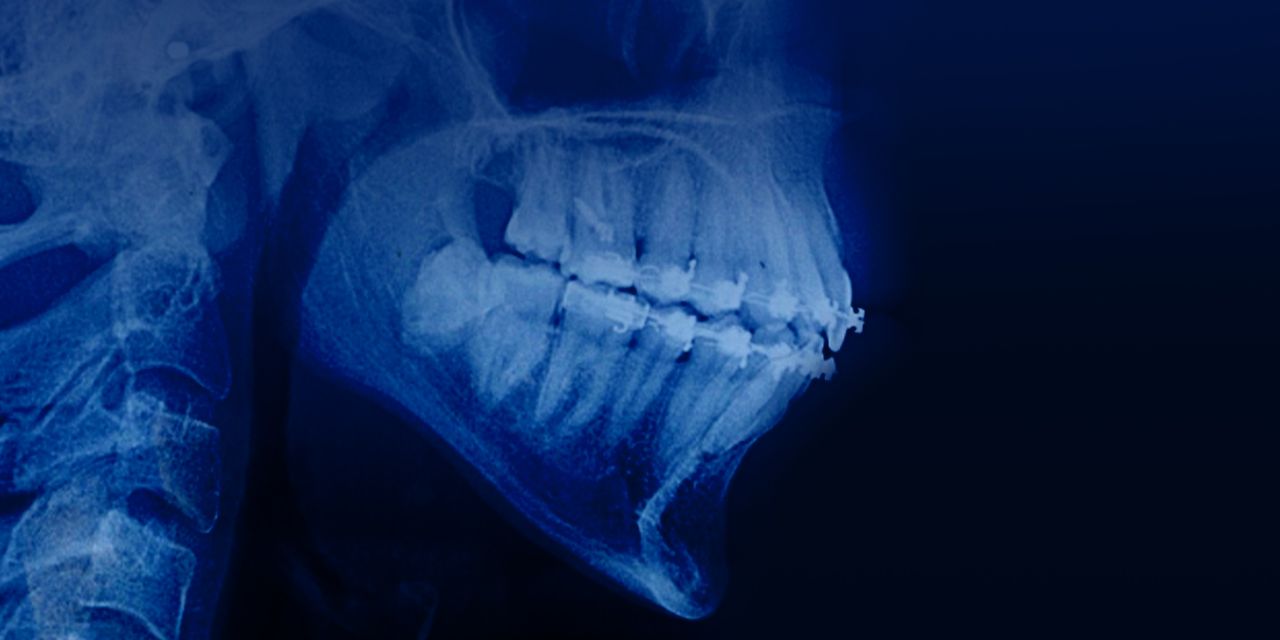

Ортодонтия как фактор расширения возможностей имплантации и протезирования

– Когда ортодонтия делает возможной имплантацию

– Обзор клинических случаев с орто-импл-ортопедией.